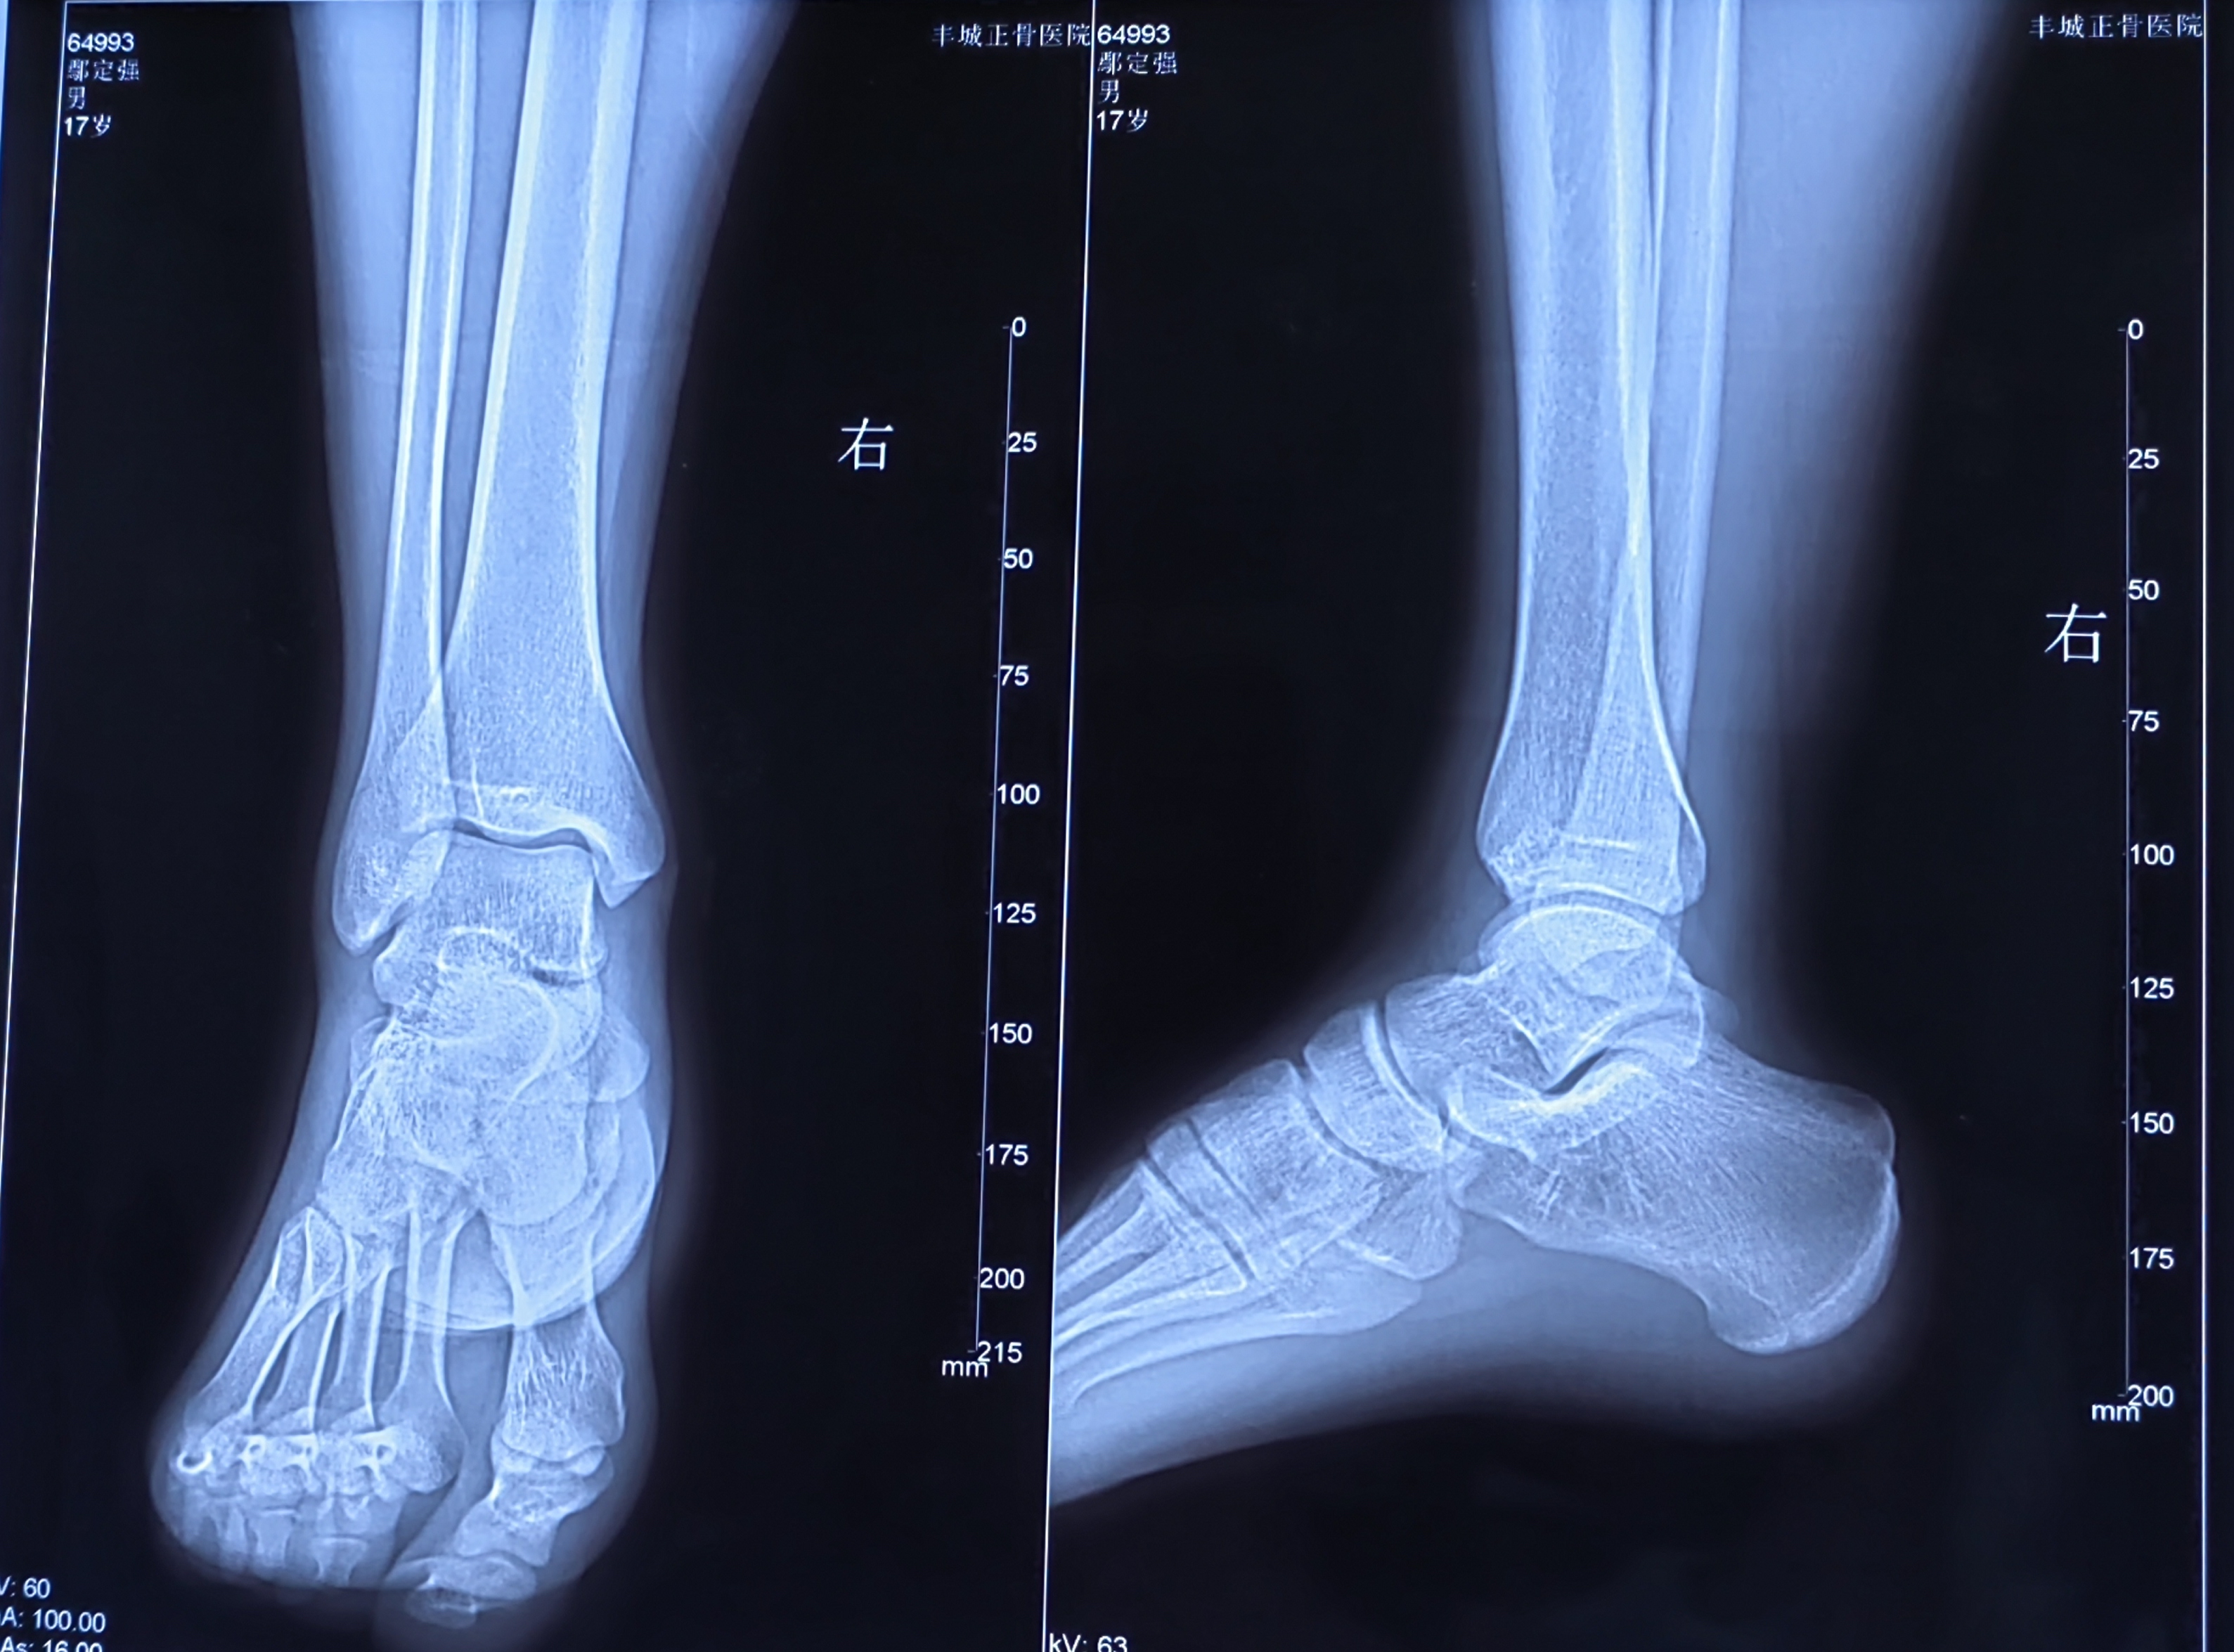

【影像】20231228丰城正骨医院X线片报未见明显骨质异常。阅片见踝关节外侧间隙未显示,考虑距骨旋转所致。20240219丰城市人民医院MRI:右踝关节距骨及胫骨远端骨髓水肿;右踝关节距腓前韧带及内侧三角韧带损伤右踝关节腔积液。

【讨论】本案为踝关节扭伤所致,症状表现为右踝肿痛不敢全力着地走路,X线片阅片见距踝关节位置异常,MRI见距骨和胫骨下端骨髓水肿、三角韧带和腓距前韧带损伤,查体见外踝前下方压痛(+),诊断为陈旧性踝扭伤、距骨+胫骨挫伤、腓距前韧带损伤。

患者二月前扭伤,踝部肿痛轻而未愈,X线片见距踝关节位置异常,仍处于错缝状态,诊断为陈旧性踝扭伤。踝关节错缝致踝部肌肉韧带处于异常张力状态。足部处于内翻态,外侧腓距前韧带处于高张状态,断端不易对合加之血运异常,故久而未愈;内侧三角韧带处于松驰态,血运丰富,断端易于对合故快速修复而愈。